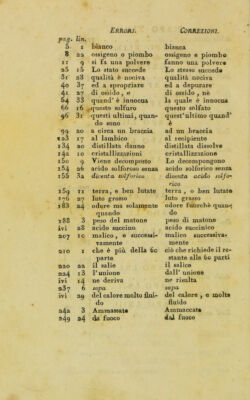

Copy 1, Volume 2

Istituzioni di chimica-farmaceutica ... / del prof. Antonio Porati ; Le quali formano il soggetto delle lezioni che fa nella scuola del Liceo dipartimentale d'Olona, stabilita nell'Ospitale Civile di Milano.

- Porati, Antonio

- 1804